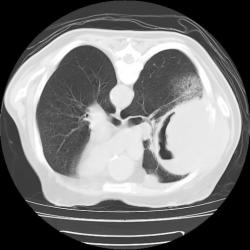

Правое легкое: в проекции средней доли (S3,4,5) определяется объемное образование преимущественно однородной структуры с ровными, четкми контурами размерами 92х88х94мм. Плотность его составляет 19-25 едН. В медиальных отделах образования содержится серповидная полоска воздуха. Латеральные отделы образования выходят за контуры грудной полости на 42 мм. На этом участке ребра не дифференцируются. Внутренний контур передней зубчатой, подлопаточной мышц размытый, граница между образованием и ними отчетливо не видна. Кзади от образования, в кортикальных отделах в легочной ткани инфильтрация. Кпереди от описанного образования расположен участок, широким основанием прилежащий к грудной стенке, имеющий плотность 12-20 ед.Н, однородную структуру, размеры 14х48мм. Прилежащее ребро интактно.

И возникла совершенно шальная мысль. А где располагается "ЭТО"? В легочной ткани или нет? и умозрительное продолжение контуров "ЭТОГО", показало, что "ЭТО" выходит за пределы грудной клетки, а именно костных её компонентов, что находит подтверждение на отдельных сканнах.

А не экстраплевральная - ли "ЭТО" пломба, которая была применена по типу "олеоторакса"?

Наблюдение на самом деле весьма редкое и интересное. Для начала; это не эхинококк и конечно не мезотелиома. Данные заболевания не дают такую скиалогическую КТ картину: полость с содержимым, серпом воздухом и с деструкцией рёбер, лопатки и инвазией грудной стенки. Такой агрессивный характер инфекции может быт при актиномикозе; но при нём идёт диффузный процесс; не характерно образование таких больших полостей с внутренними включениями.

Аспергиллус может расти инвазивно и вызывать деструкцию в костях; есть отдельная форма: инвазивный аспергиллёз... Я прикрепил ниже сканы аспергиллёза с инвазией основания черепа. Но для неё не характерно образование полостей с "грибковым шаром"... Это признак мицетемы (отдельная форма аспергиллёза). Если поразмыслить логически; должен быть субстрат; а потом уже "сел" гриб. Я думаю дело было так; у пациента есть в наличии мелкоклеточный рак лёгкого или туберкулёзная полость; а потом присоединился аспергиллус и мы получили представленную картину. По другому никак не укладывается. ИМХО.